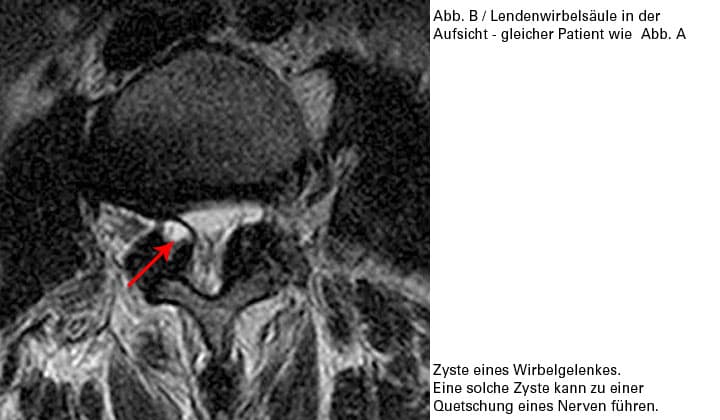

Überlastungsreizungen können in den Wirbelgelenken einen Reizerguss auslösen. In seltenen Fällen kann dieser Reizerguss bewirken, dass sich die Gelenkschleimhaut wie ein Bruchsack durch die Gelenkskapsel vorstülpt und eine Synovialcyste bildet. Diese kann eine Nervenwurzel quetschen und muss u. U. operiert werden.